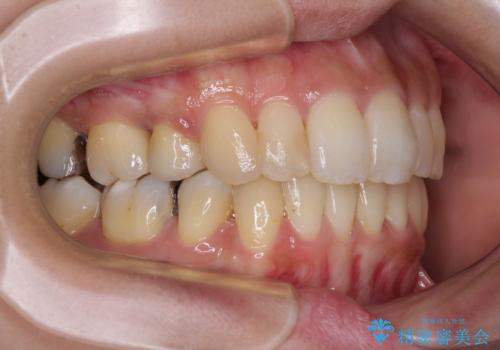

後戻りで突出した前歯をインビザラインで解消

- 抜歯矯正の後戻りで前歯が突出してきていることを気にして来院された患者様です。

口元の突出感を改善するにあたり、抜歯矯正は行うことができないため、奥歯の後方移動とIPR(歯と歯の間を削る)により達成することとしました。

再度後戻りしたときに対応しやすいよう、インビザラインにて矯正治療を行うこととしました。

舌の突出癖がなかなか改善できず、IPRによる前歯の隙間が閉じきらずに、予定よりも長い治療期間となりました。